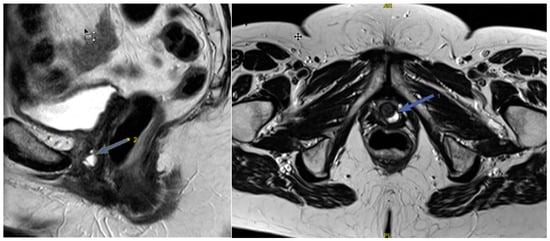

Figure 4. (a)—Normal location of the bladder floor, urethral axis, and cervix in relation to the PCL at rest—the bladder floor is located 1.3 cm above the PCL (green line) and cervix is located 2.5 cm above the PCL (red line); (b)—during pushing—the bladder floor shift slightly down; the urethral axis is vertical (green arrow), the urethral lumen does not gape; the cervix is 8 mm above the PCL (red line).

At rest, the bladder floor is located 2 cm above the PCL. The urethral axis is vertical at rest and may shift slightly when pushing, and the urethral lumen does not gape. At rest, the cervix is 4 cm above the PCL. When pushed, the cervix is 8 mm above the PCL with the H and M lines lengthening slightly while pushed (Figure 4 and Figure 5).